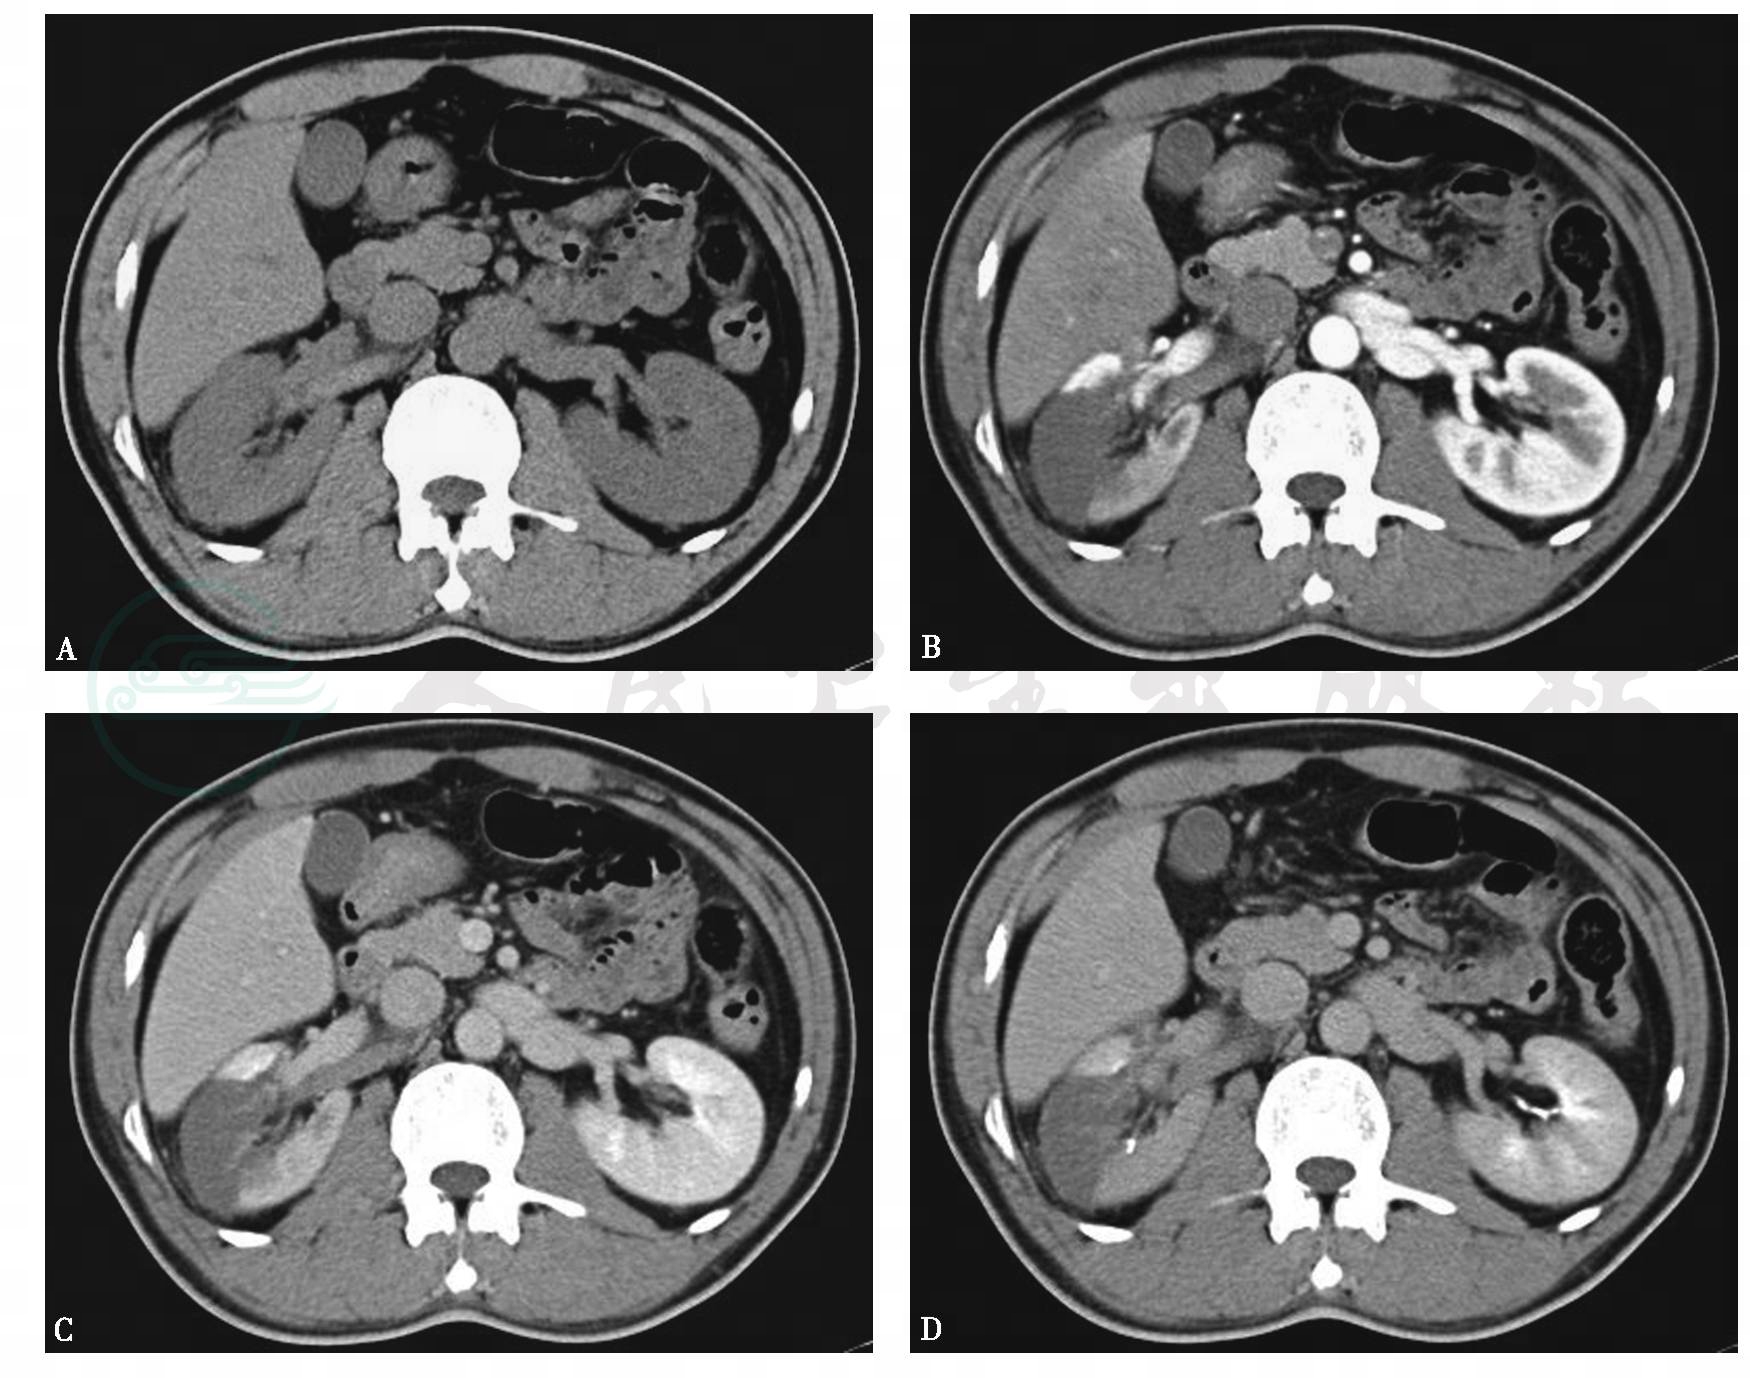

图2右肾动脉栓塞并肾梗死

A.平扫,右肾动脉增粗,密度增高,呈白血管征,同侧肾周可见条状密度增高影;B~D.增强,右肾中部可见扇形无强化区,尖指向肾窦,肾动脉内可见充盈缺损

引自:泌尿系统多层螺旋CT诊断学.第1版.ISBN:978-7-117-24109-0.主编: